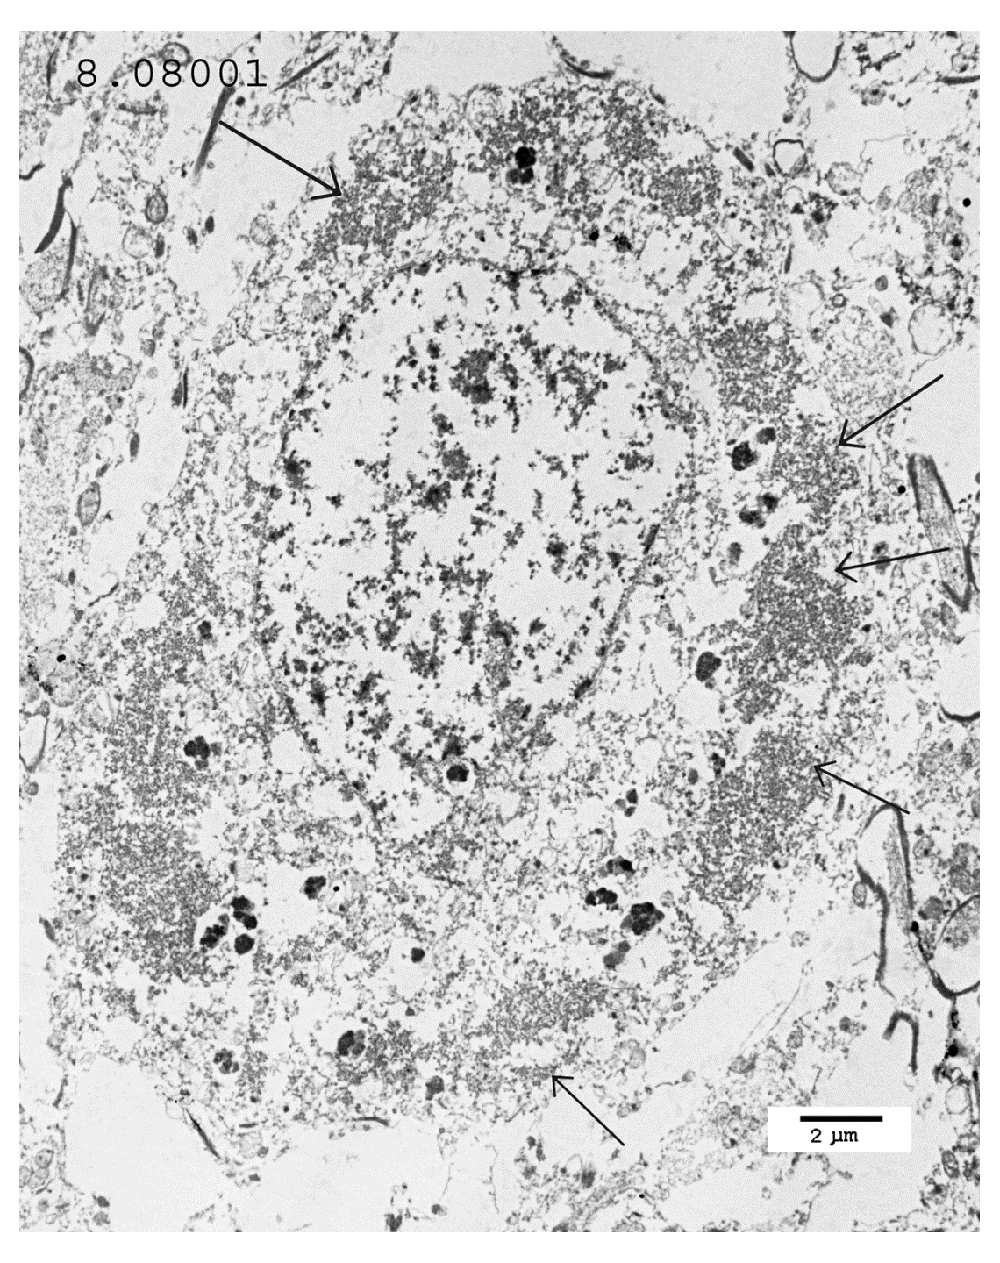

TEM changes were observed in the brainstem neurons in the PD cases and in the spinal cord motor neurons in the poliomyelitis cases. TEM of PD neurons at low magnification showed advanced apoptosis. There were almost ‘empty’ nuclei with clumped chromatin and multiple cytoplasmic virus factories. Few cytoplasmic organelles remained (Figure 1 and Figure 2). VLP were found by TEM in the nuclei and cytoplasm in the neurons of all the PD cases studied. The VLP were similar in morphology to the VLP we described in the brain of encephalitis lethargica, which had been confirmed to be a strain of enterovirus by molecular analysis1. The cytoplasmic virus factories in PD neurons consisted of large numbers of VLP interspersed with irregularly shaped endoplasmic reticulum membranes and embedded in virus factory (Figure 3 and Figure 4). VLP were observed attached to the membranes (Figure 3). The average measurements of the cytoplasmic VLP in Figure 3 and Figure 4 were both 31 nm (Table 1). Cytoplasmic virus factories in other PD neurons consisted of incomplete VLP at an early stage of assembly (Figure 5, see Discussion).

Low magnification of a neuron in the substantia nigra. The nucleus is almost devoid of chromatin and the remaining chromatin is clumped. Many virus factories are present in the cytoplasm (arrows). The black granules in the cytoplasm contain melanin. A high magnification of this image that shows intranuclear VLP is in Figure 4.

Low magnification of a motor neuron. Cytoplasmic virus factories are shown (arrows). The nucleus shows severe apoptosis.